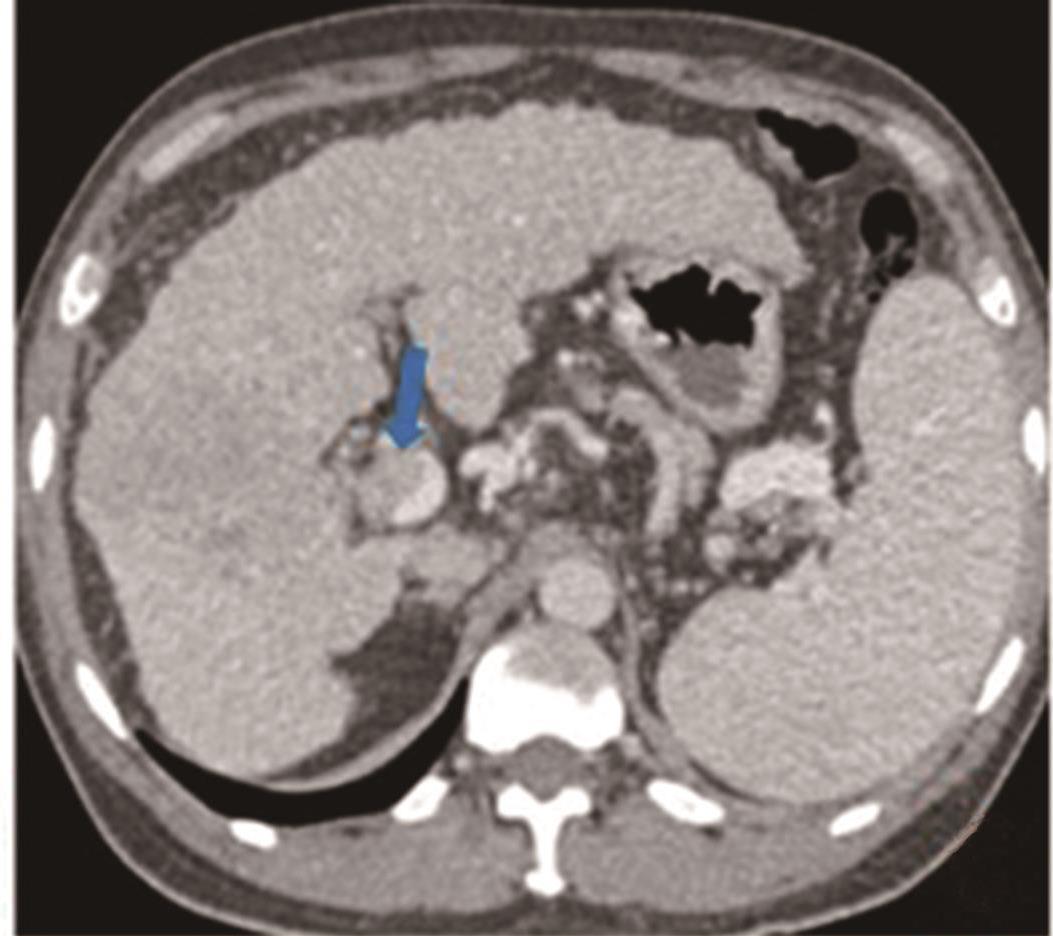

• 探讨增强CT在鉴别胆囊癌侵犯肝脏与肝癌累及胆囊病变中的应用价值

摘要:目的 探讨增强电子计算机断层扫描(computer tomography,CT)在胆囊癌侵犯肝脏与肝癌累及胆囊病变中的鉴别诊断价值。方法 收集2012年2月到2022年2月重庆医科大学附属第一医院115例患者临床及影像学资料,其中胆囊癌侵犯肝脏病例69例,肝癌累及胆囊病例46例,记录性别、年龄、肿瘤大小、肿瘤边界、胆囊形态、肝硬化、胆管扩张、肿瘤内或胆管系统内高密度影、门静脉癌栓、强化方式、强化程度、淋巴结肿大及远处转移共13个观察指标,并进行统计学分析。结果 性别(P=0.007)、年龄(P=0.002)、肿瘤大小(P=0.003)、肝硬化(P<0.001)、肿瘤内或胆管系统内高密度影(P=0.013)、门静脉癌栓(P<0.001)、强化方式(P<0.001)及淋巴结肿大(P=0.034)有统计学差异。通过回归分析筛选出年龄(敏感度为0.812,特异度为0.457)、肿瘤大小(敏感度为0.630,特异度为0.696)、门静脉癌栓(敏感度为0.326,特异度为0.957)、淋巴结肿大(敏感度为0.681,特异度为0.522)为显著分类指标,联合4个观察指标的参数绘制受试者工作特征(receiver operating characteristic,ROC)曲线,曲线下面积(area under the curve,AUC)为0.770,敏感度为0.674,特异度为0.826。结论 增强CT在鉴别胆囊癌侵犯肝脏与肝癌累及胆囊病变时,性别、年龄、肿瘤大小、肝硬化、肿瘤内或胆管系统内高密度影、门静脉癌栓、强化方式及淋巴结肿大有鉴别价值,同时结合年龄、肿瘤大小、门静脉癌栓及淋巴结肿大有助于提高鉴别诊断能力。